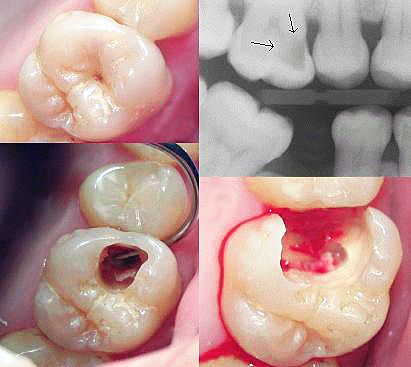

Zubni karijes

Zubni karijes je infekcija koja nastaje djelovanjem bakterija u usnoj šupljini, a najviše je potpomognuta hranom bogatom ugljikohidratima. Bakterije razgrađuju šećer, pri čemu nastaju kiseline koje smanjuju pH vrijednost u ustima. Kada se pH vrijednost snizi (5,2 – 5,5) kiseline počinju rastapati caklinu zuba što uzrokuje karijes.

Stomatolog prvo mora ukloniti karijes i doći do zdravog dijela zuba, kojeg potom mora ispuniti kako bi se zaštitia pulpa i kako bi zub mogao biti funkcionalan.

Liječenje karijesa

Klasičnom terapijom, karijes se svrdlom odstranjuje sa zuba, no uvijek se žrtvuje i zdravo zubno tkivo, a može doći i do iritacije živca.